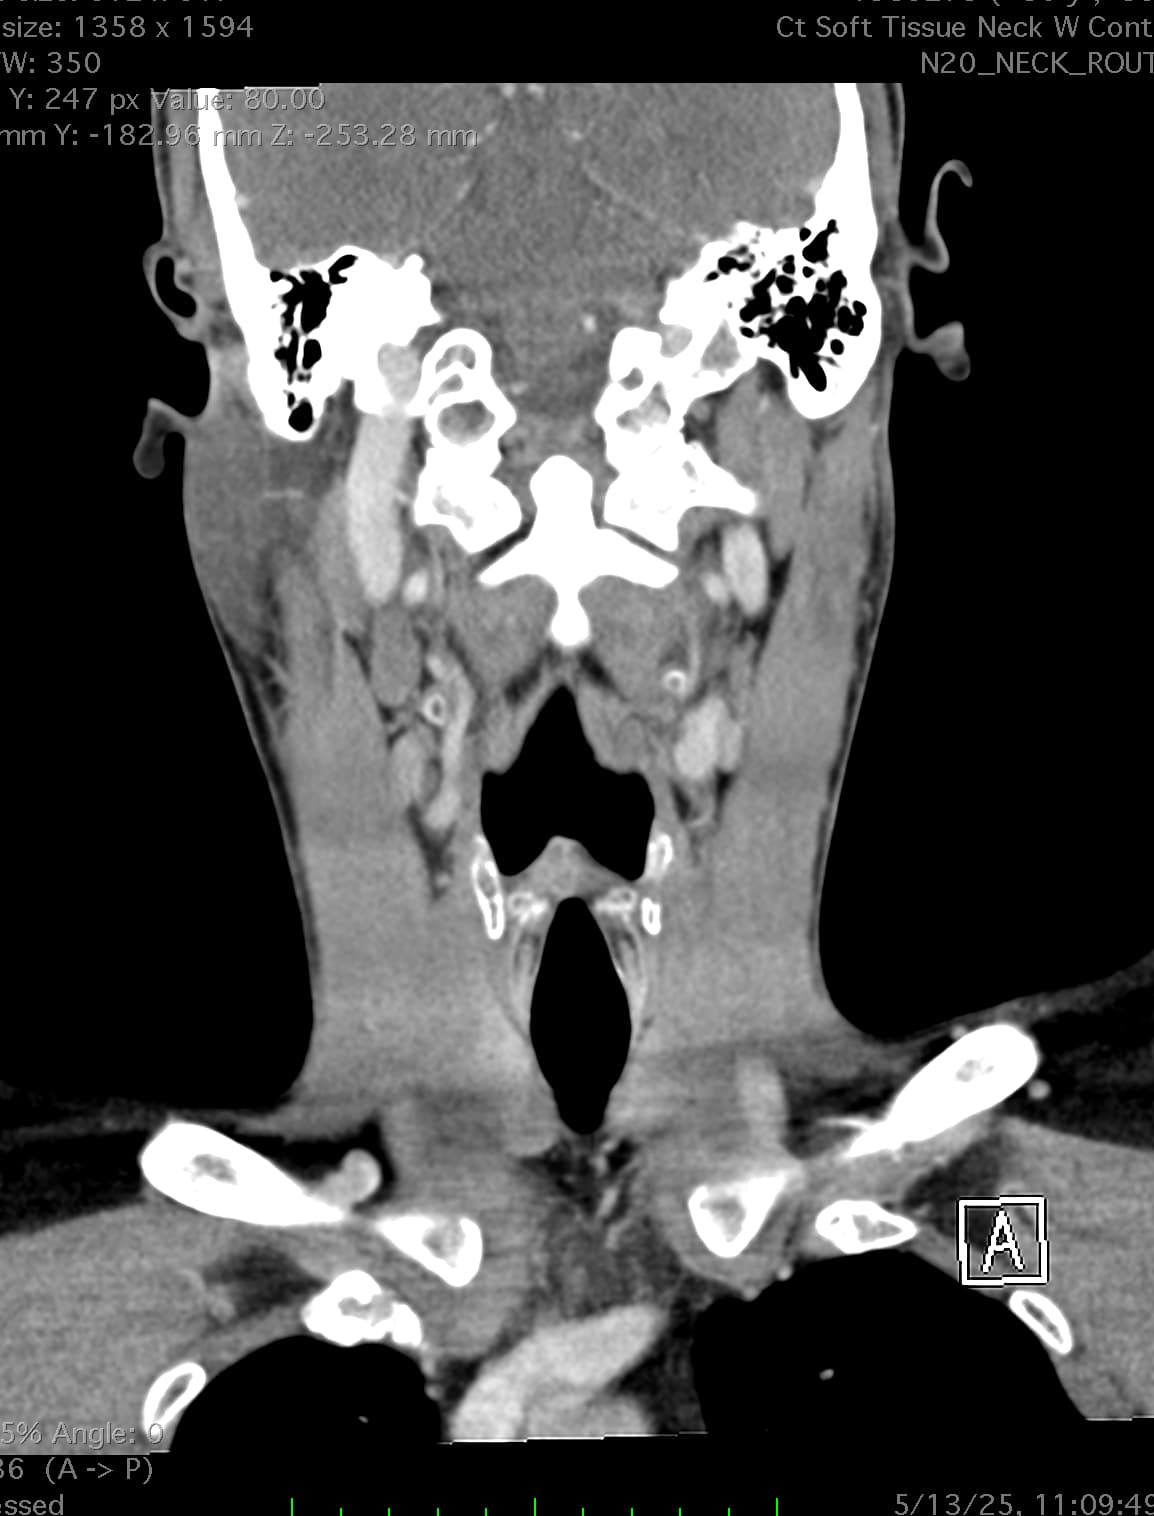

So, 2 years ago was the first time I came across Living with Eagle, filled with descriptions of all my symptoms, and a slew of scans showing very obvious bone chunks in the neck. Since I studied bio in college, and these bones are obvious, I figured I’d take a stab at looking at my own past scans and, low and behold, mild–but present–ossification of my stylohyoid ligament. Perhaps more relevant in my case, in the process of learning enough of the anatomy to understand axial images I noticed another weird thing–my right external carotid artery is in the wrong place. Instead of sitting lateral to my hyoid greater cornu, it’s medial. Hmm.

Tonsil surgery did solve the problem of my tonsils hurting, because they were gone, but no resolution of other symptoms. This was a year ago. I’ve been to PT, SLP, and now back to PT while I trial gabapentin for the neurologist. PT#2 discovered a bunch of significant atrophy in my upper right shoulder/back, and, you guessed it it’s all right sided. I’ve since then, thanks to radiopedia and Netter’s, also explored my images and noticed a few other anomalies in my scans, including an extended right thyroid superior cornu which appears to be pressing strongly into my neck also in the general area of pain, and an occipital artery branching off and wrapping around the internal carotid. Frustratingly these also weren’t mentioned on rads reports. My swallow study by the SLP showed obvious asymmetry with my swallow, but the SLP reported it symmetric and radiology apparently doesnt read the A/P view in their modified barium swallow studies? This is not inspiring faith in the academic institution I attended, but what can I possibly know they dont?

I’m here cause I’ve learned so much, and ya’ll seem to be the internet experts of weird head/neck issues adjacent to the stylohyoid chain. The docs keep seeing me, and keep ordering imaging, and seem to not be talking to each other at all? Frankly it seems to me the answers are in already in the images… so I’ve included several, perhaps you’ll see something helpful and can offer a suggestion… I just know I’m exhausted, frustrated, in so much pain all the time I cannot function which is so demoralizing, and it’s getting worse despite physician recommendations.

I wish I had better words for my existing doctors, or a doctor to visit familiar with these symptoms, if they’re sufficiently connected. Here are some scans for those interested, maybe someone has some ideas I can share with one of my doctors. I’m definitely at a loss and the pain constant and debilitating.